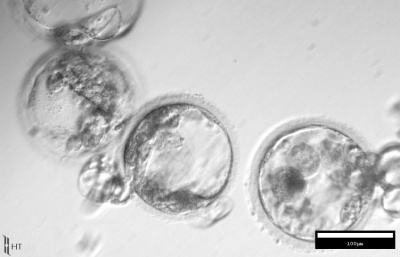

ԱՄՆ-ում կլոնավորել են հասուն մարդկանցից վերցված բջիջները

ԱՄՆ-ում գիտնականներն առաջին անգամ կլոնավորել են հասուն` 35 և 75 տարեկան տղամարդկանցից վերցված բջիջները: Time ամսագրի տեղեկացմամբ, վերջապես հաջողությամբ են պսակվել Advanced Cell Technology հետազ ...